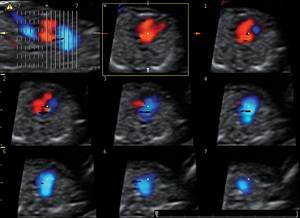

Figure 4. Complete endocardial cushion defect diagnosed at 12 weeks - first trimester echo was triggered by abnormal ductus venosus alone, during routine screening.

This component of first-trimester screening is just now coming to the forefront. Its availability can benefit populations at high risk of cardiac anomalies (such as women who have long-standing diabetes). It may be especially beneficial to those who were in poor glycemic control at the beginning of their pregnancy. It appears, though, that the exam can be meaningfully applied in low-risk populations as well. Research is underway to determine the best approaches to counseling and to determine which patients should have subsequent invasive testing.

It wasn’t long ago that second-trimester fetal echocardiography was the gold standard for any prenatal evaluation of fetal cardiac structure and function. Now, with an early and integrated screening approach that utilizes first-trimester fetal cardiac examination, we can in fact diagnose many of the most severe heart defects as early as 12 weeks of gestation. At this stage, the fetal heart is as small as the tip of the little finger.

Indeed, significant improvements in the overall computing capability of modern ultrasound equipment, in three-dimensional color ultrasonography, and in ultrasound image resolution – as well as specific new technologic developments such as tomographic imaging and spatiotemporal image correlation – have opened the door to first-trimester cardiac screening.

In the majority of patients, up to 12 parameters of fetal cardiac structure can be visualized. Each of the three segments of the exam takes only a few seconds to perform, so the actual collection of information is rapid. The technologic advances have also made the acquisition of images easier and less operator dependent. Moreover, the analysis is then performed offline, so the mother can go home afterward. Offline analysis of images also means that the ultrasound scan itself can be performed by trained sonographers at a distance from a cardiac center, with the information transmitted to the center for expert analysis.